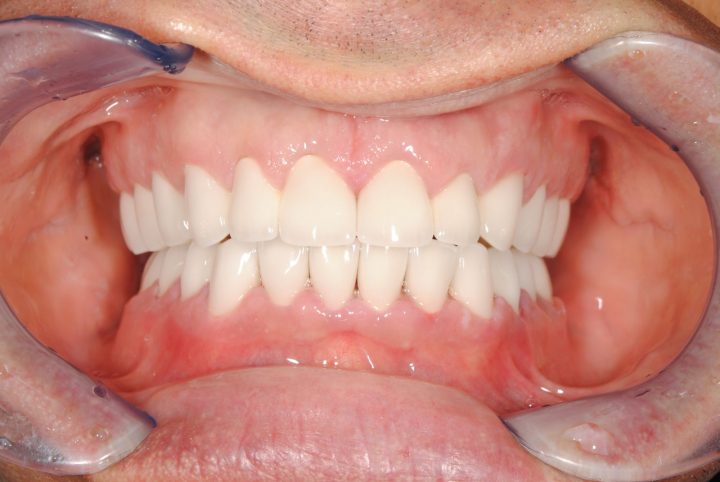

Garreth ist ein englischer Synchronisationsschauspieler. Der Zustand seinen Zähnen hat die Lautbildung und seinen Gesundheitszustand schon seit langem gestört.

Wegen seiner Arbeit war die herausnehmbare Prothese ausgeschlossen, weil die Lautbildung und die Sprache sich verändern würden.

Zu gleicher Zeit wurden die obere, zweiseitige Knochenaufbau und die obere Implantation im Kauen Region durchgeführt. Auf beiden Seiten haben wir schweizerische Straumann Implantate, Premium Qualität benutzt.

Er hat unten, in die Kauenregion 2-2 Implantate bekommen. Nach der 6 Monate lange Heilungszeit wurden metallfreie Zirkonkronen auf den Frontzähnen bearbeitet, und auf Implantate Metallkeramik Kronen hergestellt.